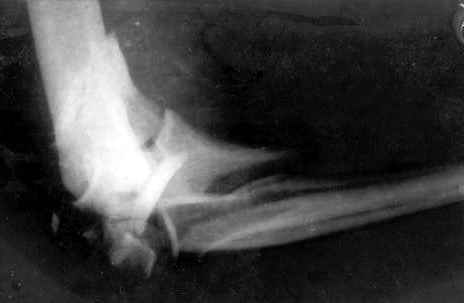

Здравствуйте, коллеги.Мужчина, 45 лет, ДТП 24.10.05. На сегодня неврологических расстройств правой кисти нет, отека нет, движения в правом плечевом и в правой кисти в полном объеме. Правый локтевой сустав сгибани 110*, разгибание 140*, наружняя ротация предплечья 45*, внутренняя 45*. Укорочение правого плеча 4 см. Больной просит у меня совет, стоит ли ему стремиться к эдопротезированию локтевого сустава.Я, к сожелению, не видел ни одного больного после эндопротезирования локтевого сустава.-- С уважением,Анатолий Борзунов

Имея небольшой опыт эндопротезирования локтевого сустава (3 операции - 2 эндопротеза типа Сиваша, и 1 - RM), считаю, что основным показанием к эндопротезированию этого капризного сустава является его гипермобильность (в результате перелома с формрованием разболтанного ложного сустава см. форум от 06.04 2006), или выраженный болевой синдром в сочетании с тугоподвижностью (что встречается у наших больных с гемофилической артропатией). Собственные результаты в целом неплохие - отсутствие болей и гипермобильности, однако, имеется некоторое ограничение разгибания. Сама

операция сопровождается мобилизацией локтевого нерва, а в условиях нарушенной анатомии сросшегося оскольчатого перелома имеется высокая вероятность его травматизации во время выделения, с вытекающими проблемами.